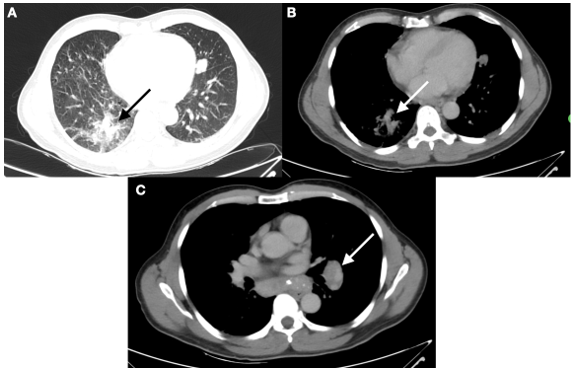

Diante do acometimento de três territórios cerebrais pelo AVC foi levantada a possibilidade de neoplasia oculta, sendo realizado rastreio amplo para neoplasia, com endoscopia digestiva alta e colonoscopia, ambas negativas. Estudo contrastado do abdome revelou nódulo hepático que poderia corresponder implante secundário (Figura 2), além de ter sido evidenciadas áreas líticas em coluna vertebral.

Figura 2: Massa hepática. Tomografia (TC) de abdome evidenciando nódulo hipodenso, no segmento VI, medindo aproximadamente 5,5 x 5,0 cm.

Foi realizada ainda tomografia de tórax contrastada cujo resultado revelava linfonodomegalias mediastinais e opacidade consolidativa cujo processo neoplásico não poderia ser descartado (Figura 3).

Figura 3: Massa pulmonar e linfonodomegalia mediastinal. A e B: TC de tórax evidenciou opacidade consolidativa, irregulares, medindo aproximadamente 4,1 x 2,7 cm, na base pulmonar direita, associadas a opacidades em vidro fosco e atelectasias regionais; C: Tc de tórax evidencia linfonodomegalia mediastinal, medindo até 5,0 x 2,5 cm.